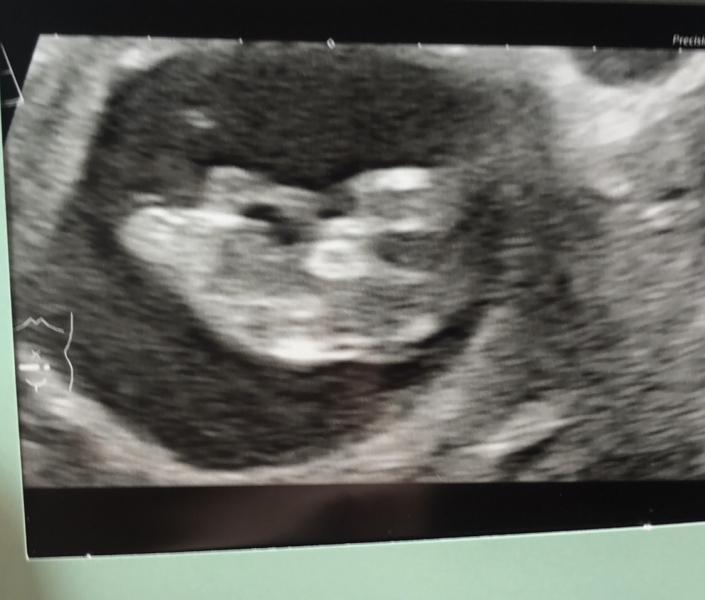

SELE97 · 16/04/2024 16:41

This scan was done last week at 10+6, my mother pointed out that you can see baby's eyes, nose and mouth but I really didn't see this before just looked like a blob to me but now I cant I see a little face. What do people think?

I have my 12 week scan tomorrow so hopefully everything goes okay and a decent photo would be a bonus❤️

@SELE97 I can definitely see eyes, nose, mouth and legs! Good luck for tomorrow!